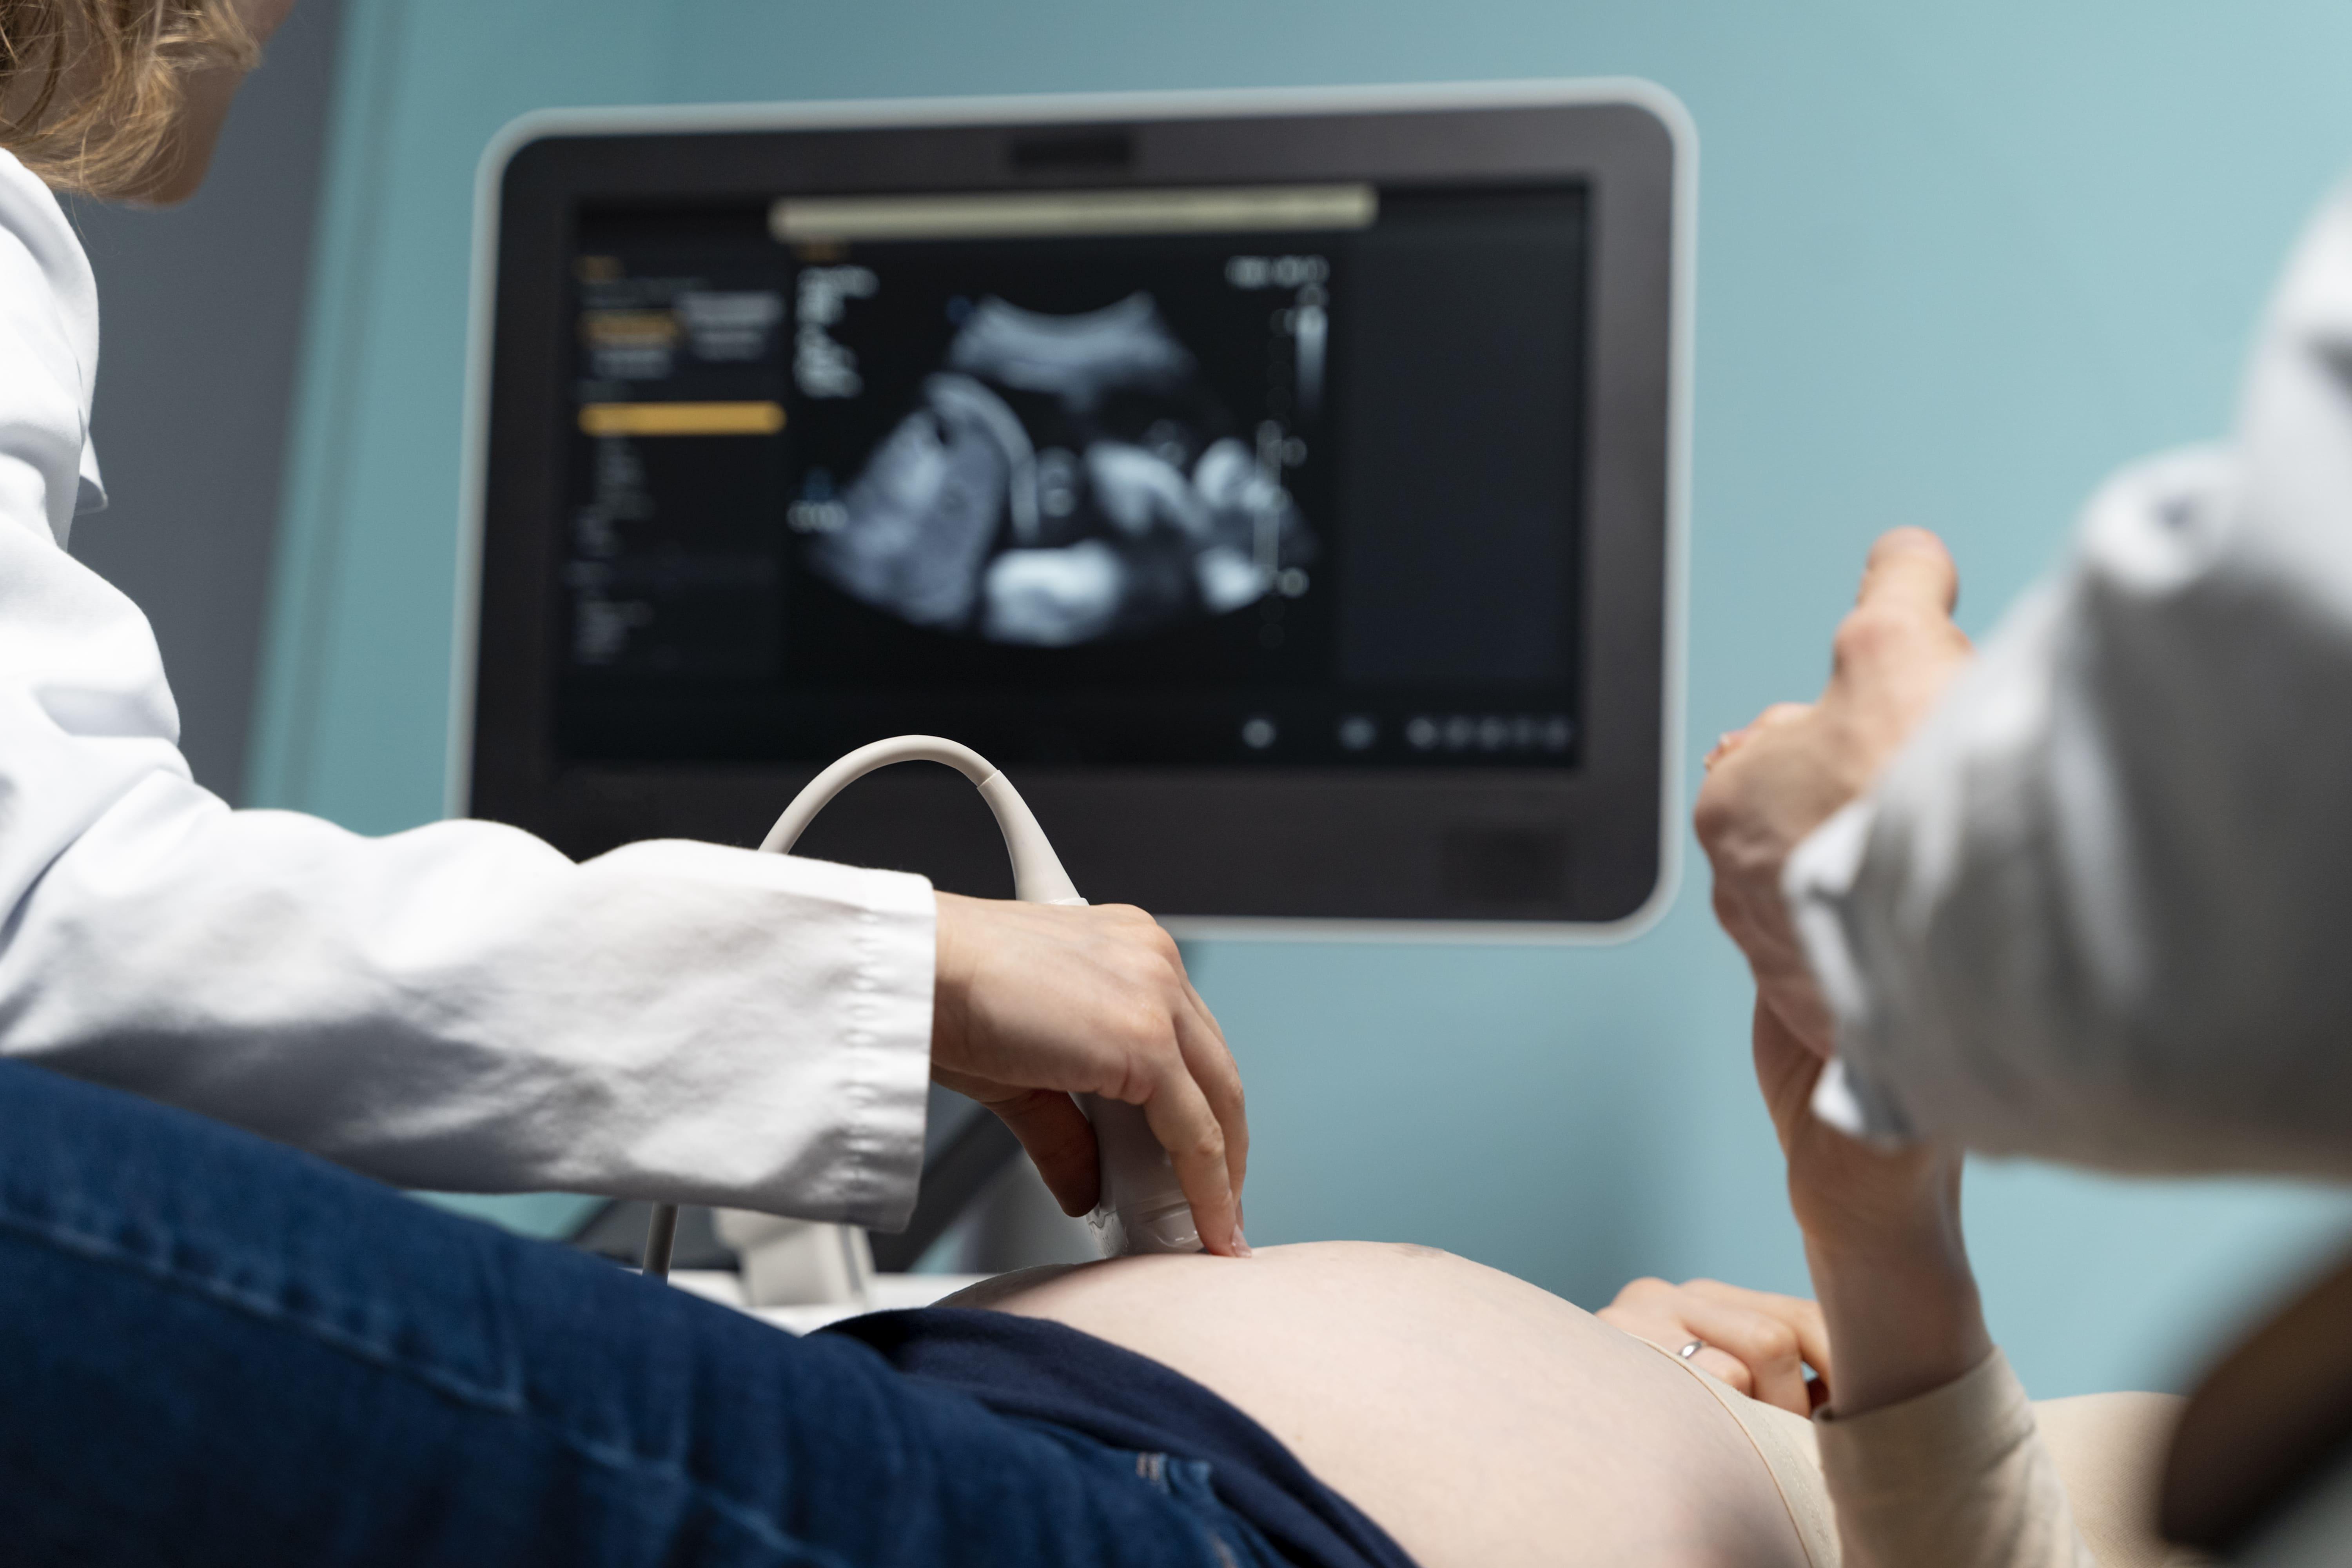

Узи это вредно

Узи это вредно 112 фото